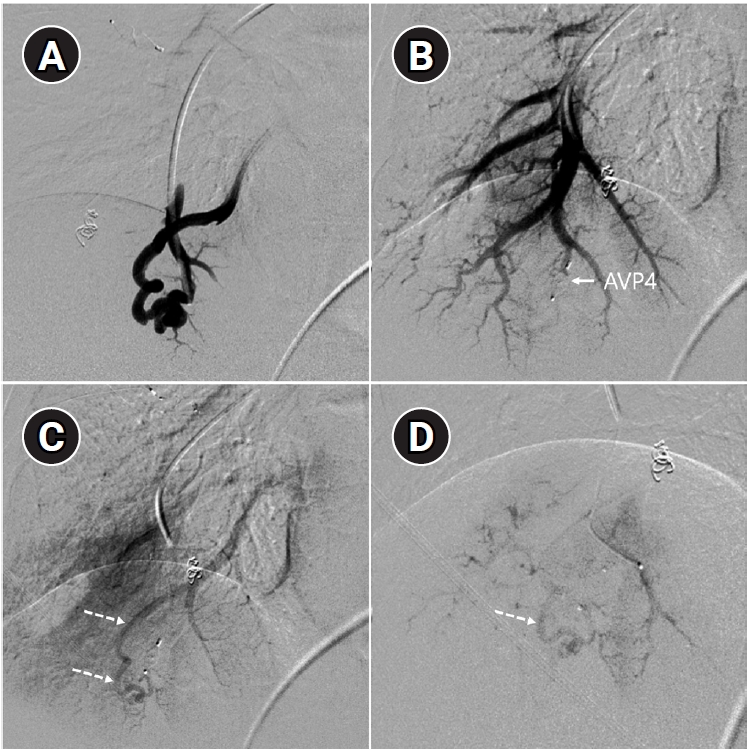

Time-resolved magnetic resonance angiography (TR-MRA) and procedural images of a pulmonary arteriovenous malformation showing recanalization. (A) In the TR-MRA performed before the procedure, a venous sac (arrow) is observed concurrently with the feeding artery (dashed arrows). (B) Recanalization was confirmed in the selective angiography. (C) Utilizing additional coils and an 8 mm Amplatzer vascular plug type IV (AVP 4) (arrow), the feeding artery embolization was carried out. (D) On the 6-month follow-up TR-MRA, the feeding artery is no longer visible, and the venous sac is also not observed.

Fig. 6. Time-resolved magnetic resonance angiography (TR-MRA) and procedural images of a pulmonary arteriovenous malformation showing recanalization. (A) In the TR-MRA performed before the procedure, a venous sac (arrow) is observed concurrently with the feeding artery (dashed arrows). (B) Recanalization was confirmed in the selective angiography. (C) Utilizing additional coils and an 8 mm Amplatzer vascular plug type IV (AVP 4) (arrow), the feeding artery embolization was carried out. (D) On the 6-month follow-up TR-MRA, the feeding artery is no longer visible, and the venous sac is also not observed.

Long-term follow-up after treating PAVMs is needed to detect newly developed PAVMs and to identify persistence or recurrent flow [10,11]. Treatment failure in PAVMs can be classified as recanalization and reperfusion. Recanalization refers to the reopening of blood flow through spaces between the previously placed embolic material (Fig. 6). Reperfusion, on the other hand, occurs when blood flow from an adjacent pulmonary artery reopens the previously embolized distal vein or venous sac (Fig. 7) [32]. As the primary follow-up modality, CT is recommended, but there are currently no specific guidelines on whether or not to use contrast enhancement [33]. It is recommended to perform an initial evaluation by CT about 6 months after PAVM embolization, and then follow-up with CT every 3–5 years thereafter (Fig. 8). In CT follow-up, the evaluation is based on the reduction rate of the venous sac or the draining vein, and the traditional criterion is that there should be at least a 70% reduction in the size of the venous sac or draining vein [34,35]. In recent studies, there have been opinions that this 70% size reduction criterion is too strict. In response, some research using angiographic-confirmed cases or time-resolved magnetic resonance angiography (TR-MRA) has proposed a 50%–60% guideline [36,37]. When using CT, repeated radiation exposure and metal artifacts from the coils can be problematic. By using metal artifact reduction techniques, it is possible to obtain clear images of the surrounding parenchyma, and this also helps in assessing parameters like the draining vein diameter reduction rate (Fig. 9) [38]. Furthermore, low-dose CT protocols may help reduce cumulative radiation exposure during repeated follow-up imaging.

In parallel, increasing attention has been directed toward the role of dynamic imaging modalities, particularly TR-MRA [39-42]. Reperfusion can be confirmed if the draining vein is observed simultaneously with the pulmonary artery on TR-MRA. Because TR-MRA can clearly distinguish between the pulmonary arterial and pulmonary venous phases, and because it is less affected by coil artifacts, it allows for a more reliable differentiation between residual arteriovenous malformation and residual sac filling caused by normal pulmonary vein drainage (Fig. 10) [41].